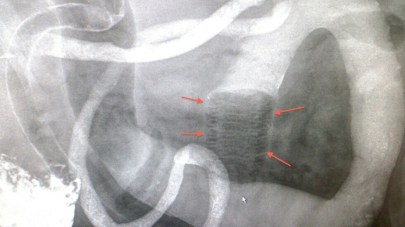

Buk: Forandringer i lever, nyre, milt, urinblære, livmor, prostata. Svulstdannelser, fremmedlegemer, leieforandringer i tarmsystem m.m.

Gassfylt livmor